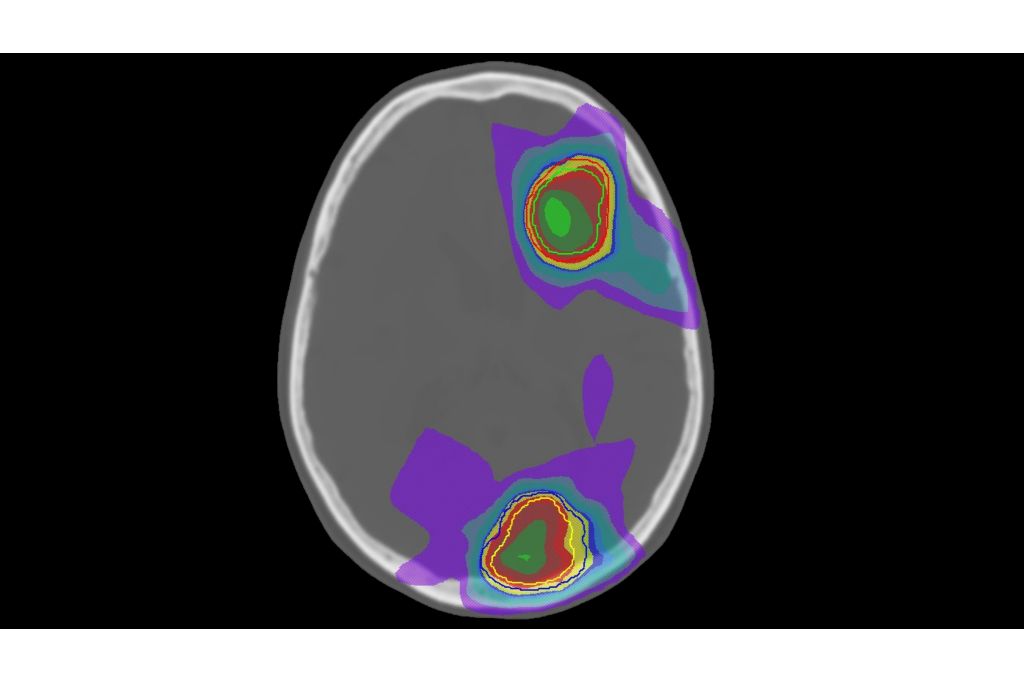

MRCAT Brain clinical application allows the use of MRI as the primary imaging modality for radiotherapy planning of primary and metastatic tumors in the brain without the need for CT. Detailed anatomical information for contouring and attenuation maps for dose calculations are both obtained from a single, submillimeter resolution 3D T1W mDIXON MR sequence. Artificial Intelligence (AI) is used for fast computation of continuous Hounsfield units directly on the MR console.

MR-only sim for primary and metastatic tumors in the brain

Single-scan approach

Automatic generation of synthetic CT images using AI

• MRCAT source scan (mDIXON XD FFE) and MRCAT-based dose plan

MRCAT source scan (mDIXON XD FFE) and MRCAT-based dose plan

MRCAT Brain lets you plan radiation therapy for patients with primary and metastatic tumors in the brain using MRI as a single-modality solution. Within just one fast MR scan, MRCAT Brain provides excellent soft-tissue contrast for target and OAR delineation, and CT-like density information for dose calculations - directly on the console. This not only extends the benefits of MRI’s outstanding soft-tissue contrast to radiotherapy planning, but it also eliminates arduous, error-prone CT-MRI registration from the process, reducing uncertainties and complexity.

With Philips MRCAT (MR for Calculating ATtenuation) Brain imaging protocol, a single mDIXON T1W scan provides information for both contouring and dose calculation for treatment planning. As anatomical and density information originate from the same scan, no image registration is required and spatial and temporal consistency are ensured.